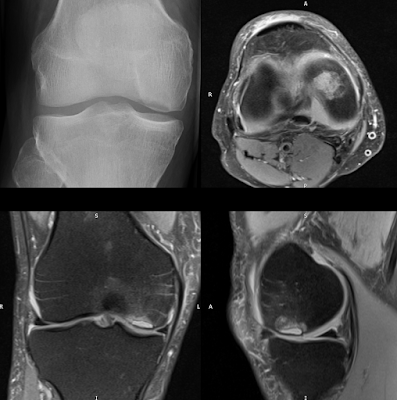

AP radiograph: circumscribed lucency of the articular surface of the medial femoral condyle.PD FS three plane: Sharp edged, well-defined joint fluid-filled defect of the articular cartilage and subchondral bone is noted in the weight-bearing surface of the medial...